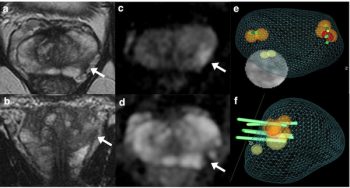

Combining multimodal imaging data and biopsy data, an artificial intelligence (AI) model provided enhanced sensitivity for defining prostate cancer tumor margins in comparison to conventional magnetic resonance imaging (MRI) assessments.